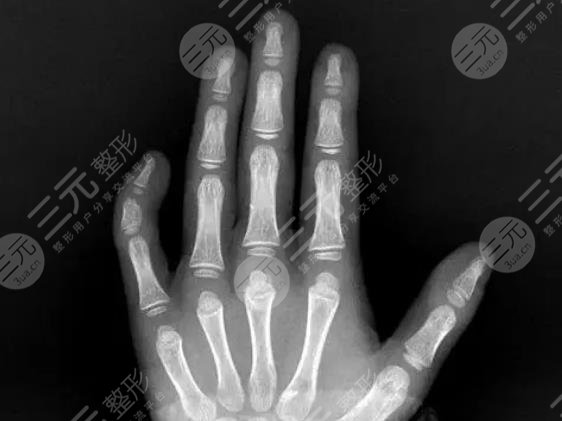

利用整形手术改良弯曲的小指自然是比较可行的,但是需要建立在规范的医生技术基础之上,根据不同原因引起的现象,选择合适的矫正方式,需要对整个小指进行明确诊断,然后再按照手术或者是非手术的缓解方式来进行改良。有些人群的小手指弯曲,由于先天性的遗传因素出现骨折或是关节炎症,那么则需要进行手术缓解。

如果是由于烫伤或者是其他的环境因素导致瘢痕萎缩而引起的小室弯曲,可以利用瘢痕切除等方式调整即可。虽说现在的整形技术比较真实,但是如果你想要改良整个小指的弯曲现象,不仅要完善整个术前的检查,也需要对整个小指头的关节部位进行适当的分析,因此建议求美者应当选择一家正规性的医疗机构进行实际操作。

一方面要选择合适的医疗机构,现阶段各地的医疗数量比较多,针对于小指弯曲的情况需要及时进行检查,如果是关节或者是其他病症所引起的小指弯曲,那么需要到正规的医院进行及时检查与缓解。如果小指弯曲只是影响到外部的形态,那么可以通过整形手术的方式来进行矫正。